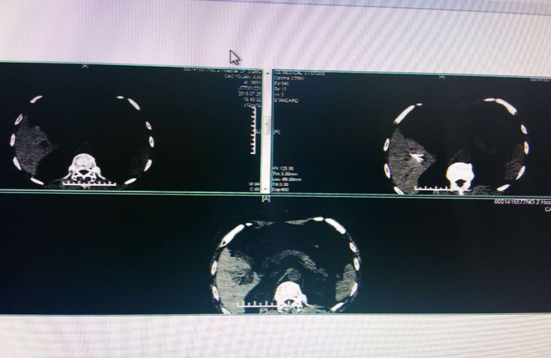

2018年7月26日,重医附二院感染与肝病中心在感染科胡鹏主任的带领下,成功完成江南院区的第一台CT引导下肝癌射频消融术。患者为老年男性,